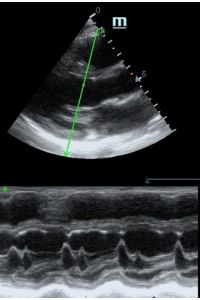

Но как же провести стандартные измерения в М-режиме, если мы его не использовали? На помощь приходит функция Free Xros M – анатомический М-режим. Имея записанную в память прибора видео петлю, мы можем провести линию М-режима в любом месте, при этом корректируя изначально не оптимальный угол.

MAPSE - амплитуда движения латерального кольца митрального клапана, позволяет рассчитать фракцию выброса по формуле EF = 4.8 × MAPSE (mm) + 5.8, очень быстрый и гораздо более точный («прародитель Strain») метод чем широко распространенный метод Teicholtz. В современных приборах можно легко добавить свою формулу при отсутствии ее в стандартном калькуляторе. Главным условием является проведение линии М-режима параллельно стенке левого желудочка в апикальном четырехкамерном сечении, что легко достигается при использовании функции Free Xros.